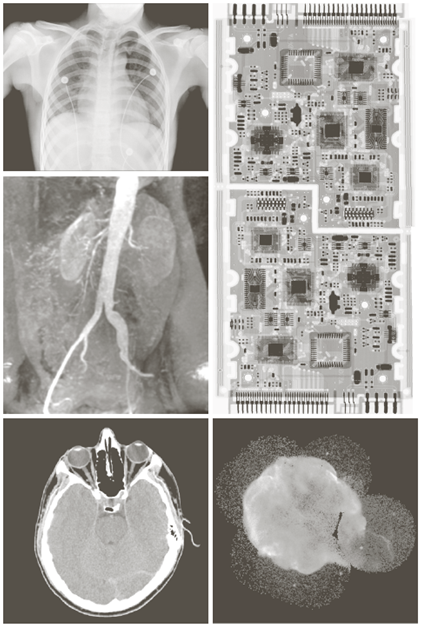

X-ray image

a) 항암제 Taxol b) 콜레스테롤 c) 마이크로프로세서

Visual band image – 영상처리에 의한 품질검사

a) 회로 기판

b) 포장 알약

c) 병

d) 플라스틱 표면의 기포

e) 씨리얼

f) 각막 이식